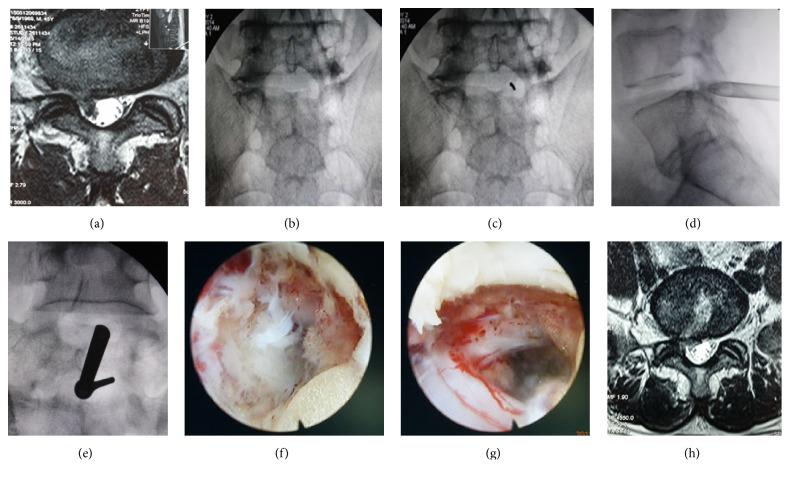

Objective is to analyze the surgical strategy, safety, and clinical results of percutaneous full-endoscopic discectomy through interlaminar or extraforaminal puncture technique for LDH. Preoperative CT and MRI were analyzed, which were based on the main location of the herniated disc and its relationship with compressed nerve root. Sixty-two patients satisfied the inclusion criteria during the period from August 2012 to March 2014. We use percutaneous full-endoscopic discectomy through different puncture technique to remove the protrusive NP for LDH. Sixty patients completed the full-endoscopic operation successfully. Their removed disc tissue volume ranged from 1.5 mL to 3.8 mL each time. Postoperative ODI and VAS of low back and sciatica pain were significantly decreased in each time point compared to preoperative ones. No nerve root injury, infection, and other complications occurred. The other two patients were shifted to open surgery. No secondary surgery was required and 91.6% of excellent-to-good ratio was achieved on the basis of Macnab criteria at postoperative 12 months. Acquired benefits are fewer complications, rapid recovery, complete NP removal, effective nerve root decompression, and satisfactory cosmetic effect as well. This is a safe, effective, and rational minimally invasive spine-surgical technology with excellent clinical outcome.

目的是分析经皮全内镜下经椎板间或椎间孔外穿刺技术治疗腰椎间盘突出症(LDH)的手术策略、安全性及临床效果。基于椎间盘突出的主要位置及其与受压神经根的关系,对术前CT和MRI进行分析。2012年8月至2014年3月期间,62例患者符合纳入标准。我们采用经皮全内镜下不同穿刺技术切除突出的髓核治疗LDH。60例患者成功完成全内镜手术。每次切除的椎间盘组织体积为1.5毫升至3.8毫升。与术前相比,术后各时间点的腰椎功能障碍指数(ODI)以及腰腿痛和坐骨神经痛的视觉模拟评分(VAS)均显著降低。未发生神经根损伤、感染及其他并发症。另外2例患者转为开放手术。术后12个月,基于Macnab标准,无需二次手术,优良率达91.6%。该手术还具有并发症少、恢复快、髓核完全切除、神经根有效减压及美容效果满意等优点。这是一种安全、有效且合理的微创脊柱手术技术,临床效果优良。